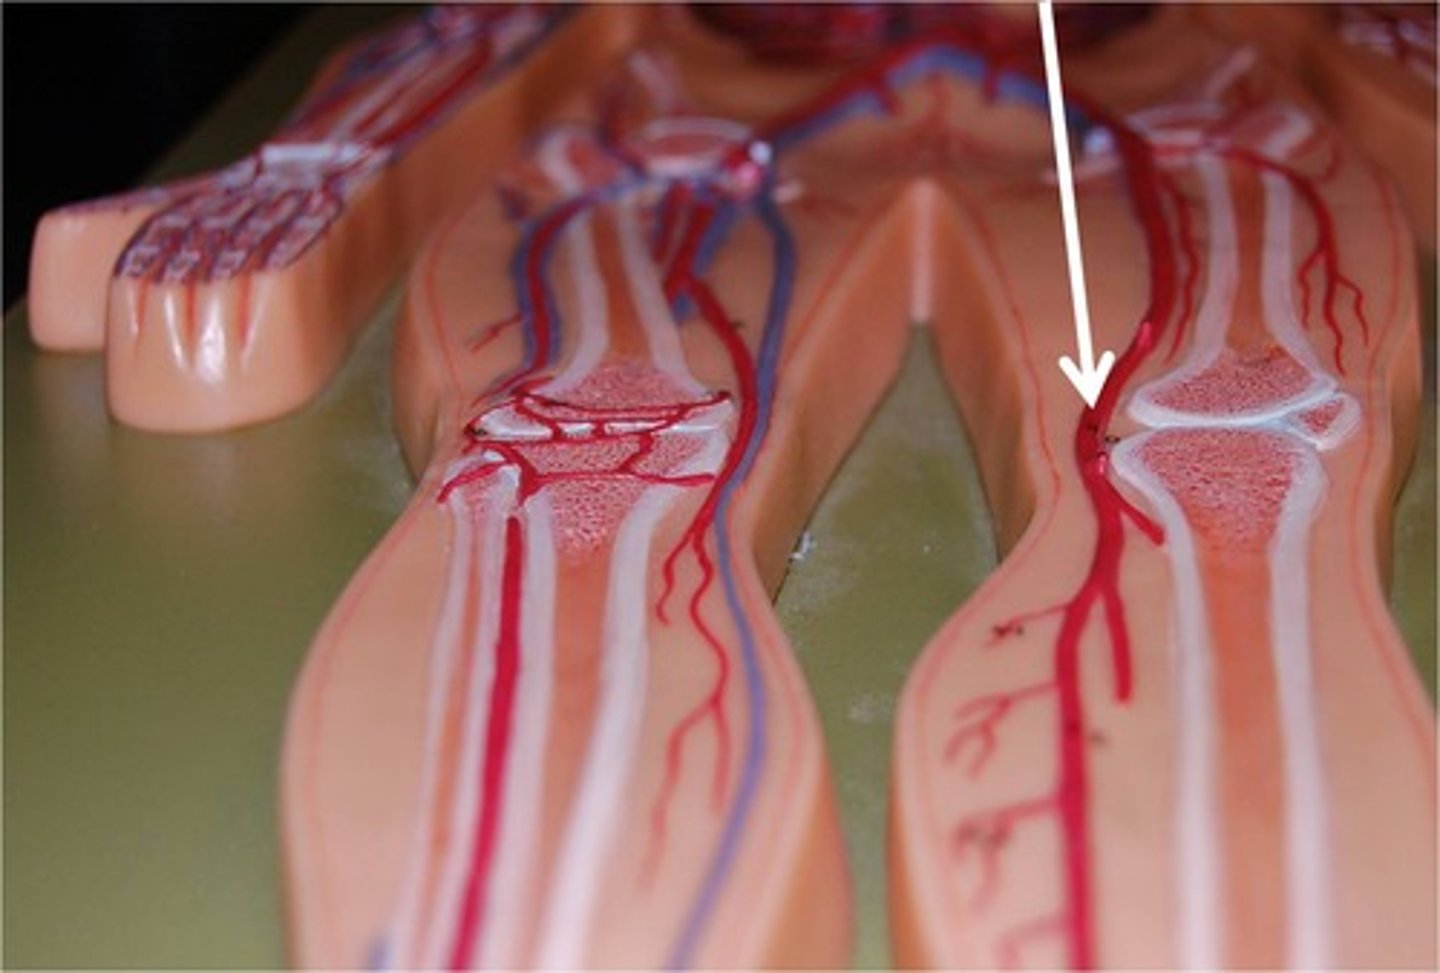

popliteal artery

feeds the posterior tibial artery, fibular artery, anterior tibial artery, and dorsalis pedis artery